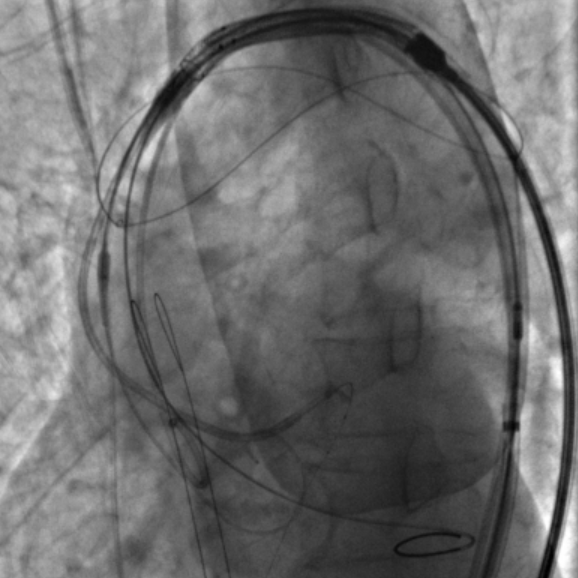

脑保护

患者既往有COPD病史,且体重极低,为避免麻醉相关并发症,麻醉方式上选择局部麻醉。在左侧股动脉上下两个穿刺点行股动脉穿刺,上穿刺点置入6F鞘管,下穿刺点置入8F鞘管。右侧股动脉切开处送入20F大鞘。沿左股动脉8F鞘,交换送入TriGUARD3™脑保护装置,透视下顺利过弓,准确定位后成功释放过滤器,全部覆盖主动脉弓的三条血管。经TriGUARD3™送入5F猪尾至升主动脉。

冠脉保护

沿左股动脉6F鞘,将JL4.0指引导管送至LM开口,送 SION 导丝至前降支远端,循SION导丝依次送Guidezilla II 延长导管和Sprinter 2.5*12m球囊至左冠内进行冠脉保护。